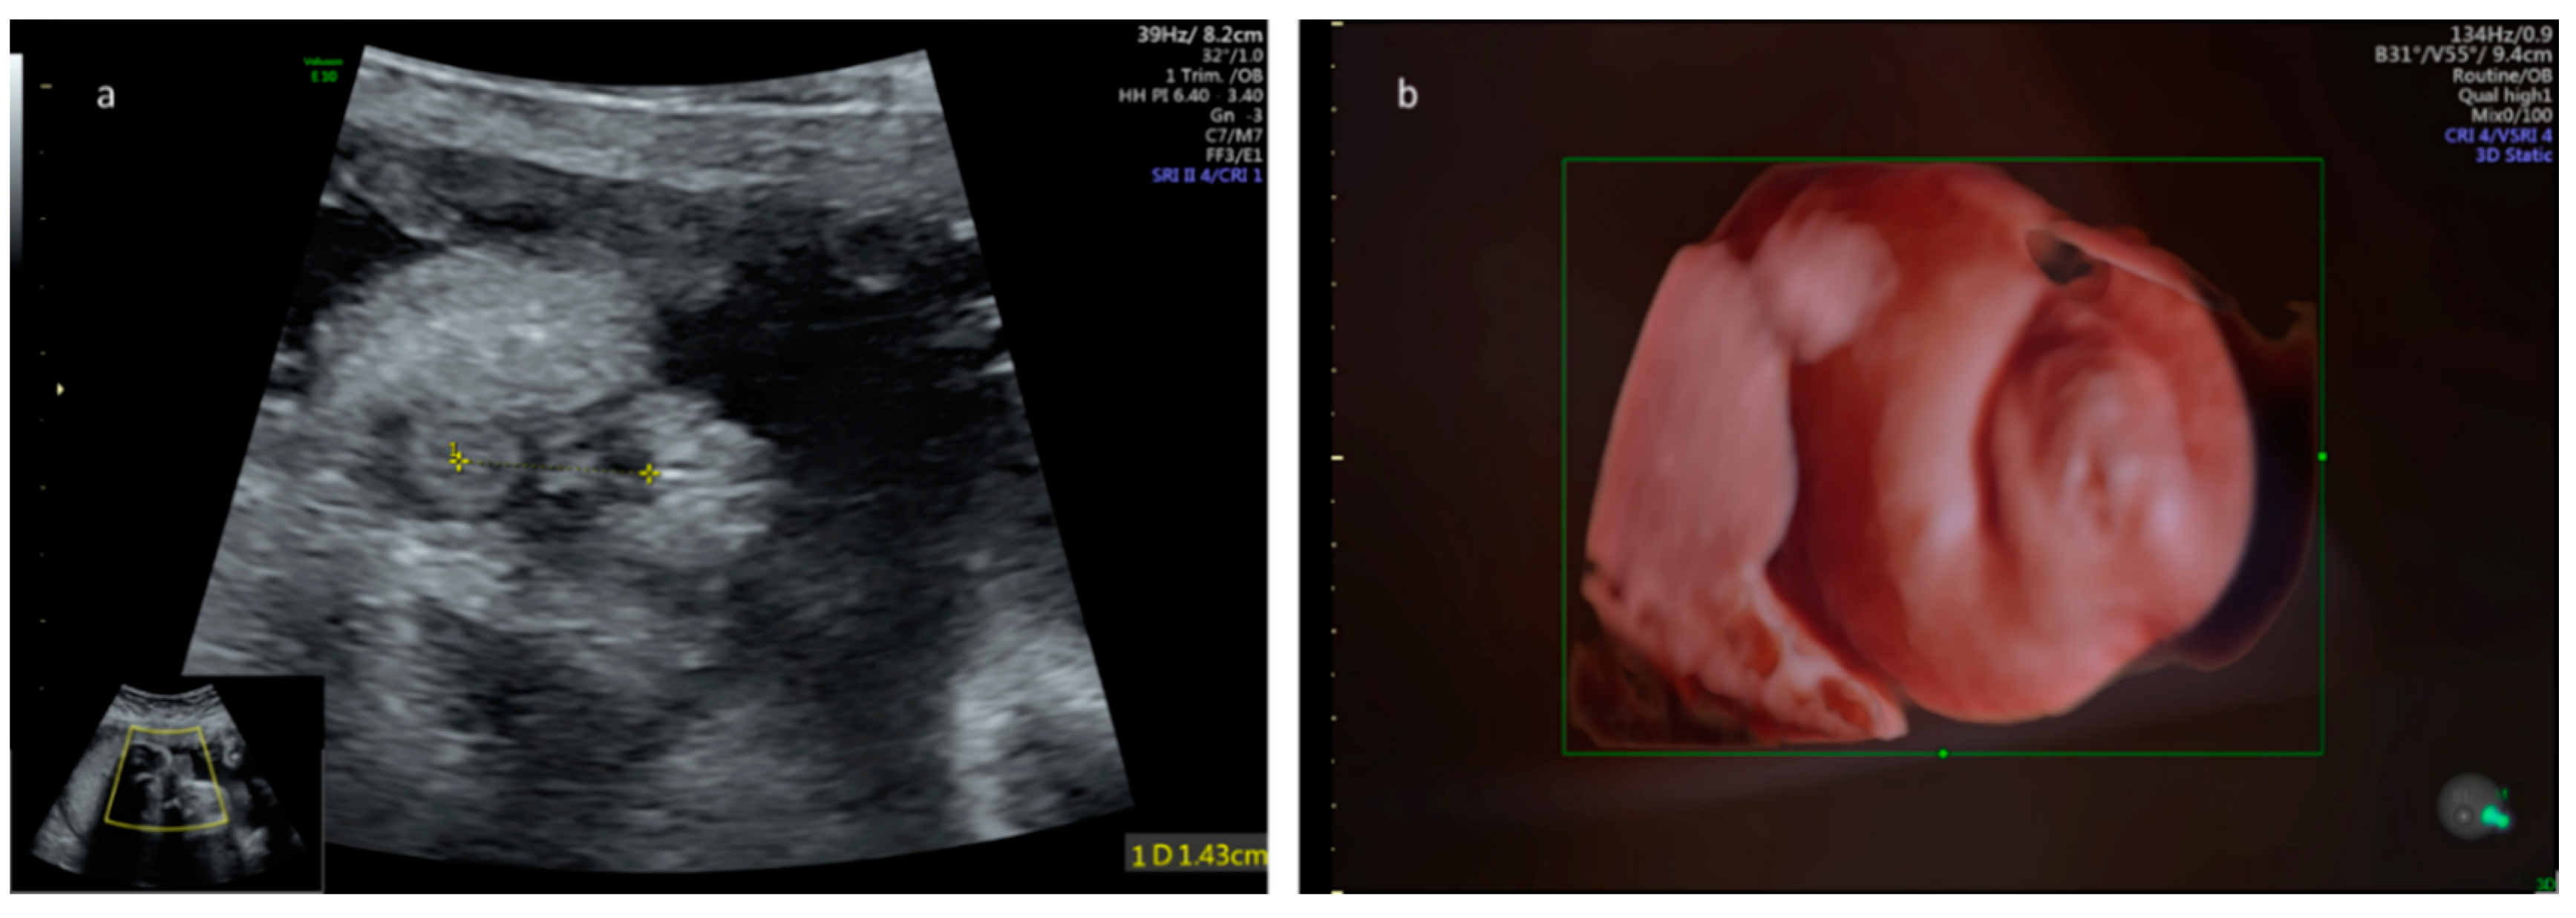

- Ochoa, J.H.; Chiesa, M.; Vildoza, R.P.; Wong, A.E.; Sepulveda, W. Evaluation of the perianal muscular complex in the prenatal diagnosis of anorectal atresia in a high-risk population. Ultrasound Obstet. Gynecol. 2012, 39, 521–527. [Google Scholar] [CrossRef]

- Perlman, S.; Bilik, R.; Leibovitch, L.; Katorza, E.; Achiron, R.; Gilboa, Y. More than a gut feeling—Sonographic prenatal diagnosis of imperforate anus in a high-risk population. Prenat. Diagn. 2014, 34, 1307–1311. [Google Scholar] [CrossRef]